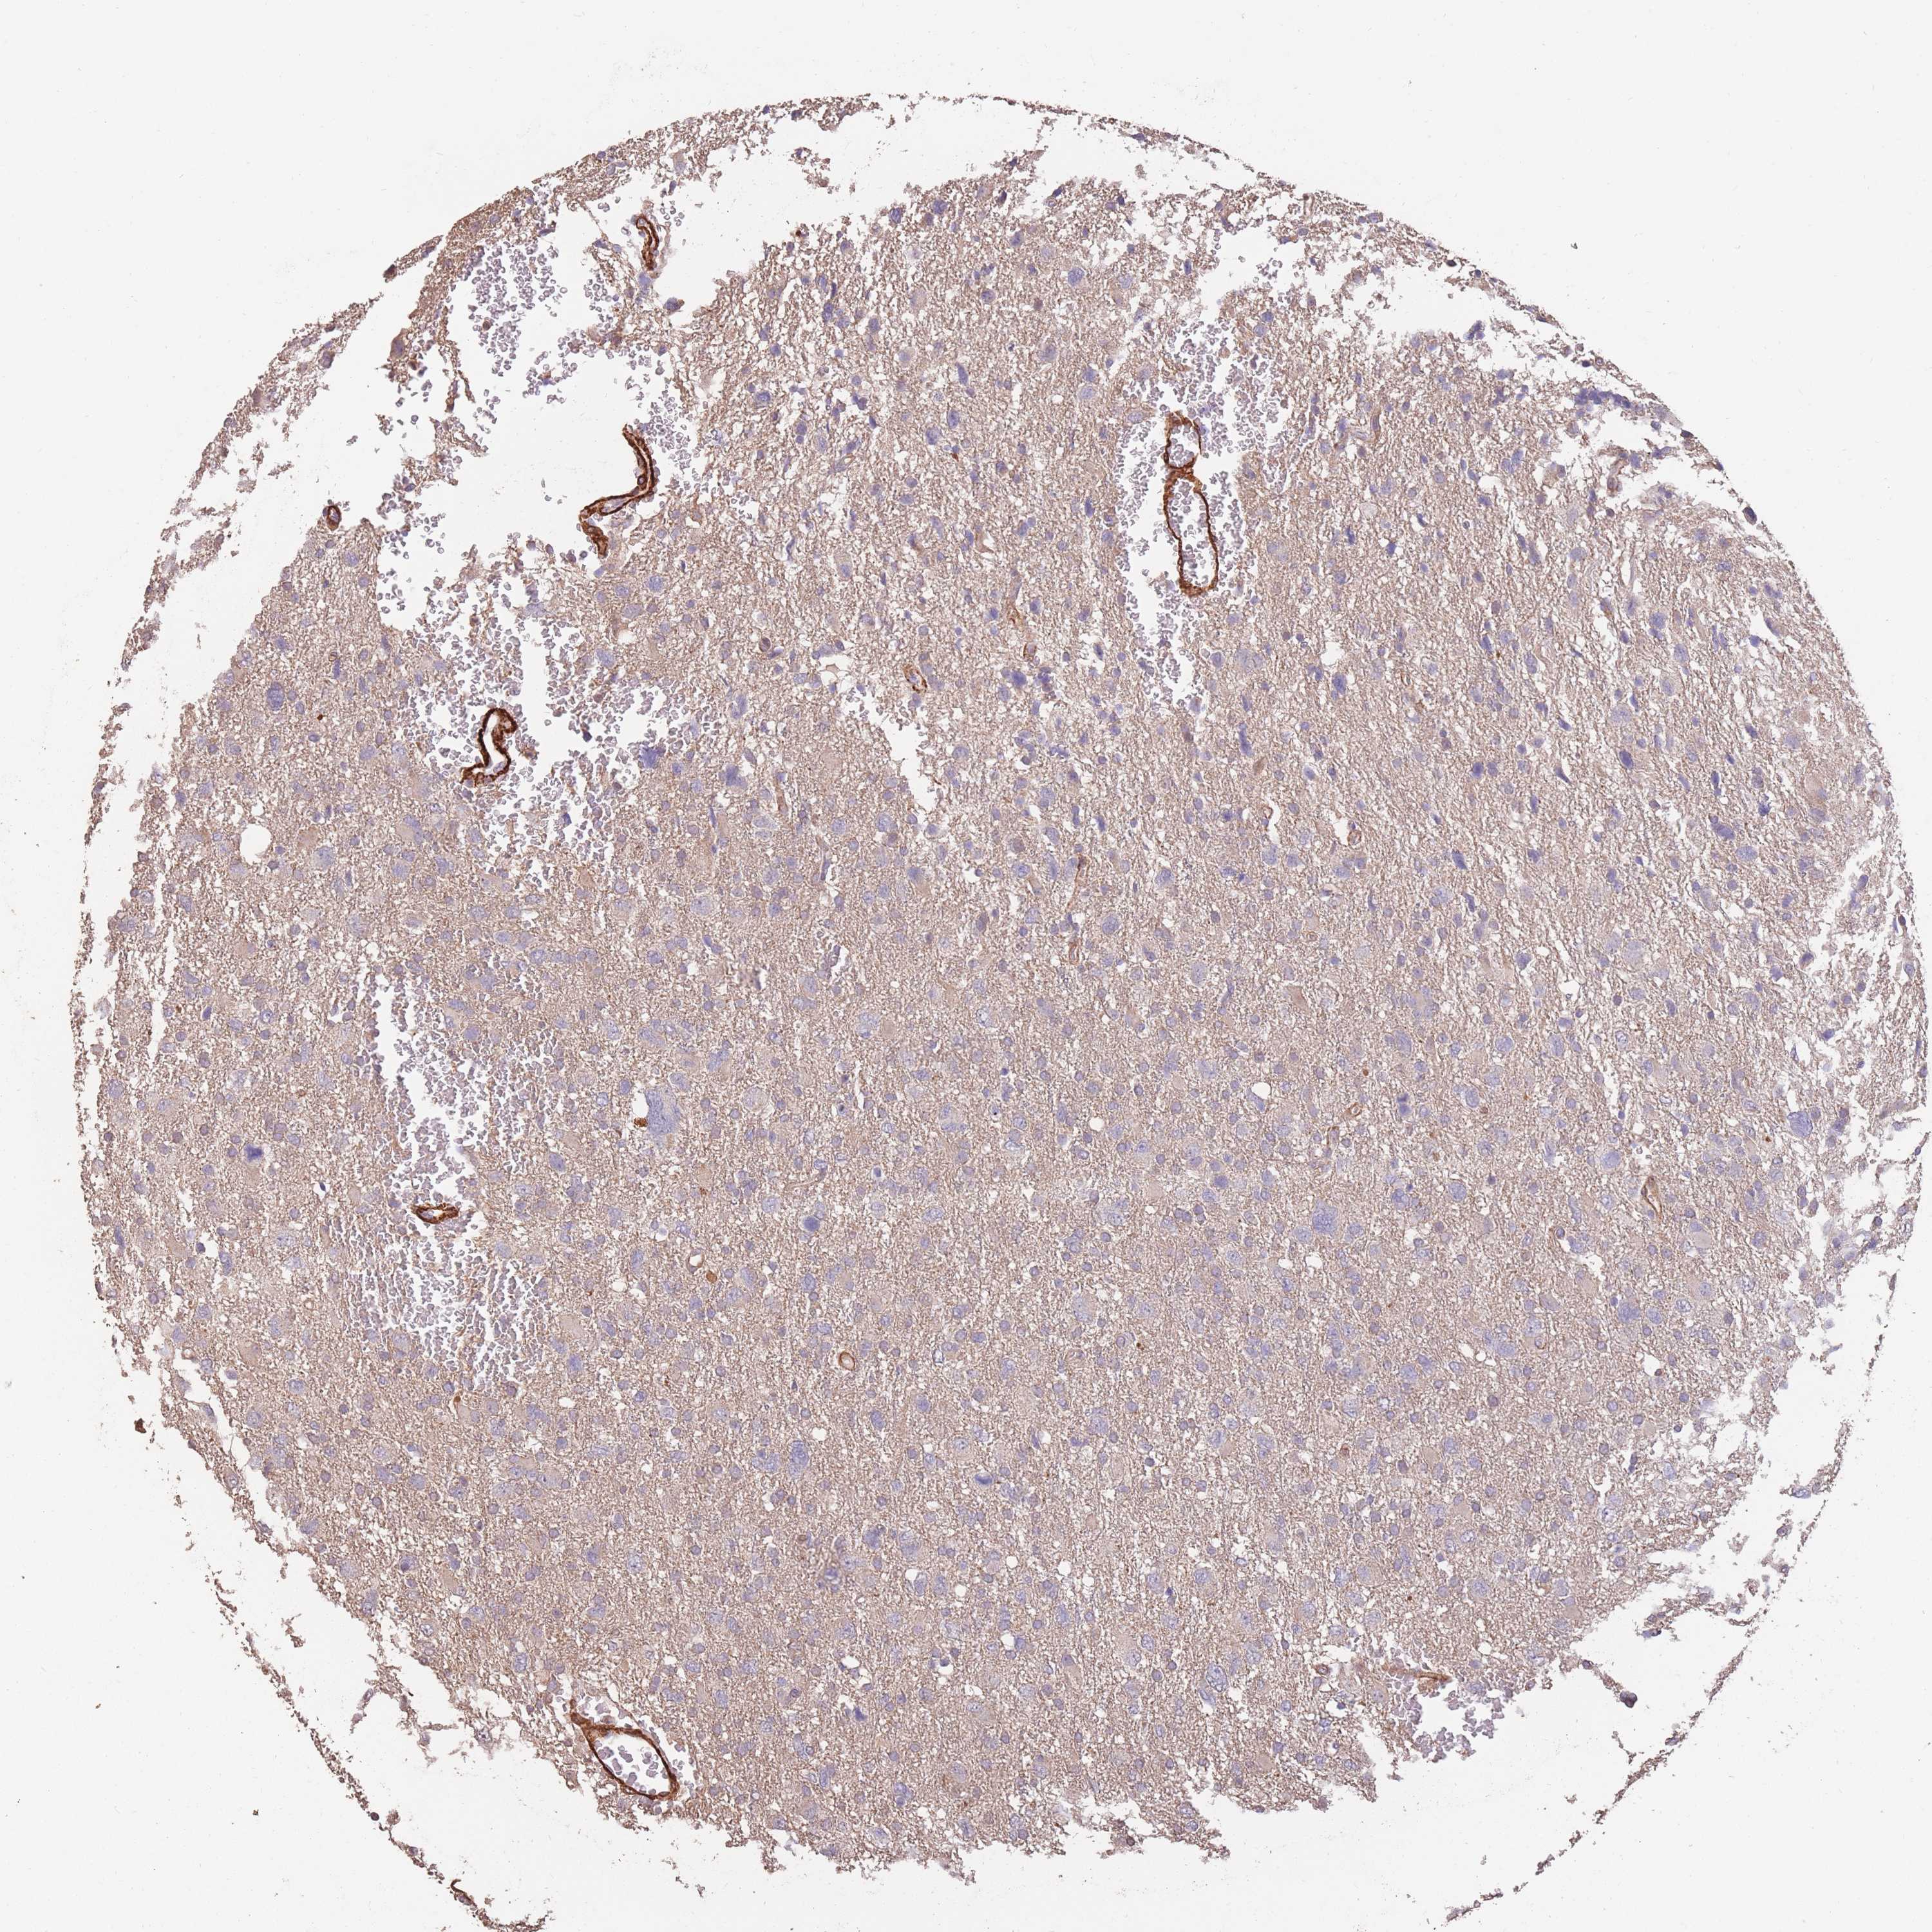

GLIOMA - Protein expressioni

A mouse-over function shows sample information and annotation data. Click on an image to view it in a full screen mode. Samples can be filtered based on level of antibody staining by selecting one or several of the following categories: high, medium, low and not detected. The assay and annotation is described here.

Note that samples used for immunohistochemistry by the Human Protein Atlas do not correspond to samples in the TCGA dataset.

Antibody stainingi

Antibody staining in the annotated cell types in the current human tissue is reported as not detected, low, medium, or high, based on conventional immunohistochemistry profiling in selected tissues. This score is based on the combination of the staining intensity and fraction of stained cells.

Each image is clickable and will lead to virtual microscopy that enables deeper exploration of all samples and also displays staining intensity scores, fraction scores and subcellular localization as well as patient and tissue information for each sample.

Antibody HPA006592

Staining

High

Medium

Low

Not detected

Intensity

Strong

Moderate

Weak

Negative

Quantity

>75%

75%-25%

<25%

None

Location

Nuclear

Cytoplasmic/membranous

Cytoplasmic/membranous,nuclear

Glioma, malignant, Low grade

Glioma, malignant, High grade